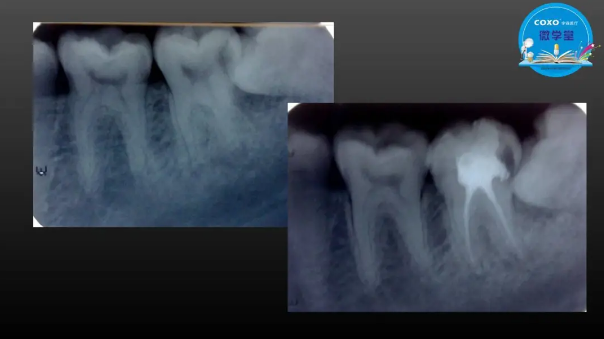

主任醫(yī)師,牙體牙髓副主任, 廣東省口腔醫(yī)院牙體牙髓科 主任醫(yī)師。2003年碩士研究生畢業(yè),研究方向?yàn)檠荔w牙髓病學(xué),擅長(zhǎng)于牙體牙髓病的診斷、齲齒、牙髓炎、根尖周病的治療以及前牙美容修復(fù)。